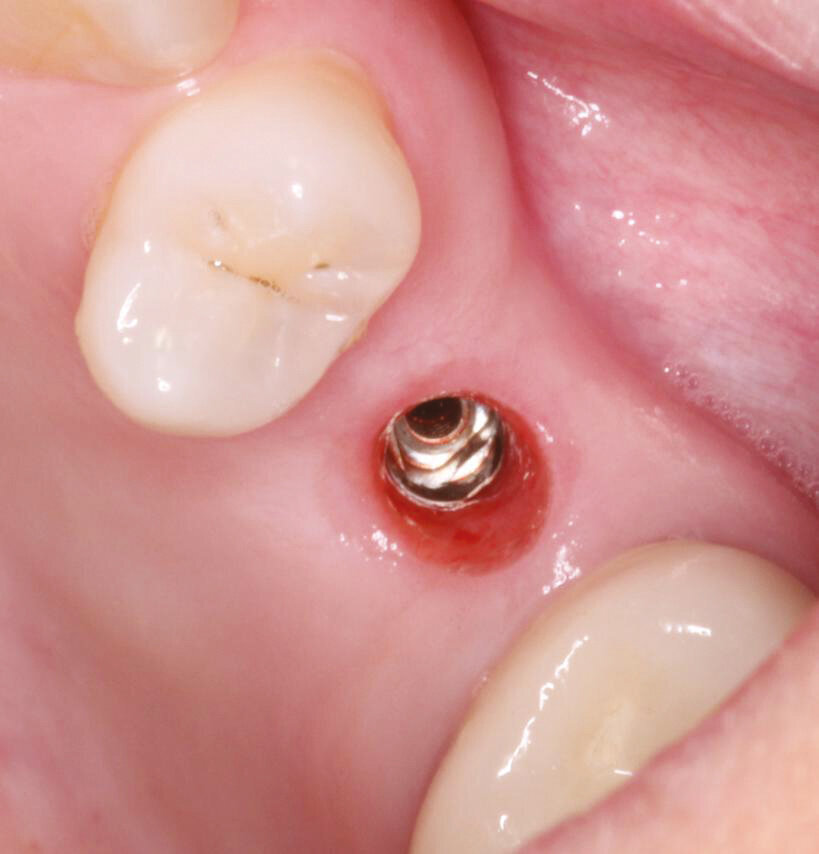

Fig.12: Heal check and Healing cap removal – note the proper tissue emergence profile and excellent health.

Fig.13: Heal check and Healing cap removal – note the proper tissue emergence profile and excellent health.

Fig.14: Stock Ti abutment selection 4 or 6 mm height.

Fig.15: Stock abutment placement with margin 0,5 mm subgingival.